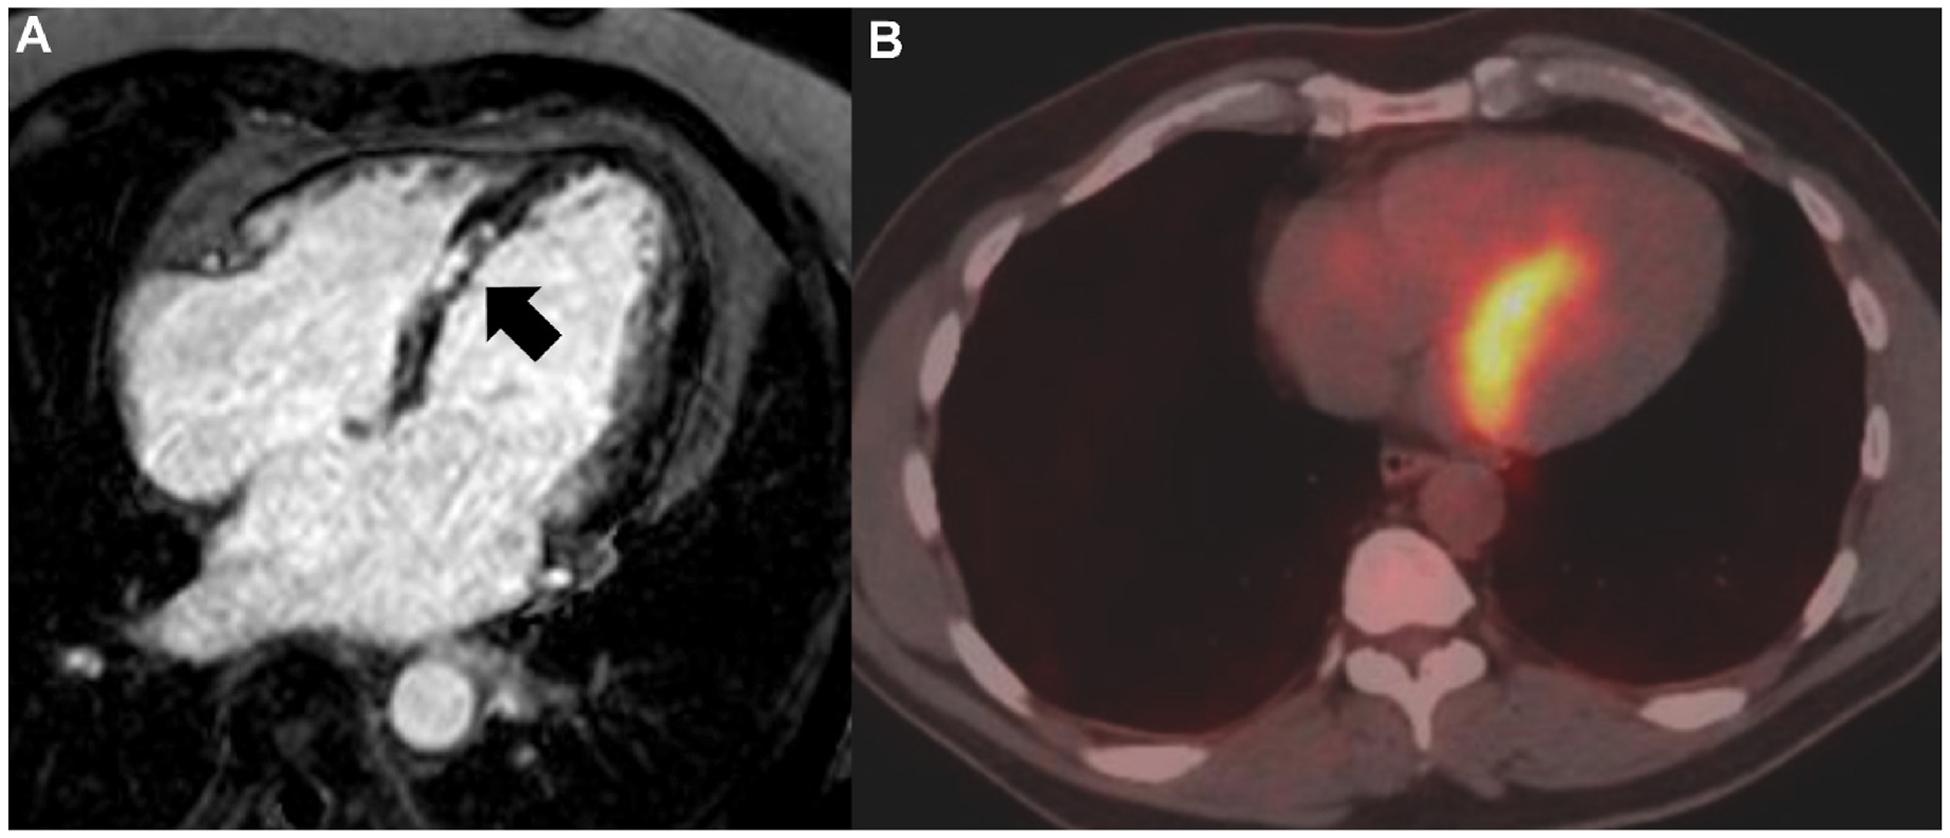

A framework for exclusion of alternative diagnoses in sarcoidosis.

Sarcoidosis is a multisystem granulomatous syndrome that arises from a persistent immune response to a triggering antigen(s). There is no "gold standard" test or algorithm for the diagnosis of sarcoidosis, making the diagnosis one of exclusion. The presentation of the disease varies substantially between individuals, in both the number of organs involved, and the manifestations seen in individual organs. These qualities dictate that health care providers diagnosing sarcoidosis must consider a wide range of possible alternative diagnoses, from across a range of presentations and medical specialties (infectious, inflammatory, cardiac, neurologic). Current guideline-based diagnosis of sarcoidosis recommends fulfillment of three criteria: 1) compatible clinical presentation and/or imaging 2) demonstration of granulomatous inflammation by biopsy (when possible) and, 3) exclusion of alternative causes, but do not provide guidance on standardized strategies for exclusion of alternative diagnoses. In this review, we provide a summary of the most common differential diagnoses for sarcoidosis involvement of lung, eye, skin, central nervous system, heart, liver, and kidney. We then propose a framework for testing to exclude alternative diagnoses based on pretest probability of sarcoidosis, defined as high (typical findings with sarcoidosis involvement confirmed in another organ), moderate (typical findings in a single organ), or low (atypical/findings suggesting of an alternative diagnosis). This work highlights the need for informed and careful exclusion of alternative diagnoses in sarcoidosis.

结节病是一种多系统肉芽肿综合征,由对触发抗原的持续免疫反应引起。目前尚无诊断结节病的“金标准”检测方法或诊断流程,这使得结节病的诊断成为一种排除性诊断。该疾病在个体之间的表现差异很大,涉及的器官数量以及单个器官的表现均有所不同。这些特点决定了诊断结节病的医疗保健人员必须考虑一系列可能的替代诊断,涵盖各种表现形式和医学专业领域(感染性、炎症性、心脏、神经)。目前基于指南的结节病诊断建议满足三个标准:1)临床表现和/或影像学表现相符;2)通过活检(如有可能)证实存在肉芽肿性炎症;3)排除其他病因,但未提供排除替代诊断的标准化策略指导。在本综述中,我们总结了结节病累及肺、眼、皮肤、中枢神经系统、心脏、肝脏和肾脏时最常见的鉴别诊断。然后,我们基于结节病的验前概率提出了一个用于排除替代诊断的检测框架,验前概率分为高(在另一器官已证实有结节病累及的典型表现)、中(单个器官的典型表现)或低(非典型/提示替代诊断的表现)。这项工作强调了在结节病诊断中明智且谨慎地排除替代诊断的必要性。